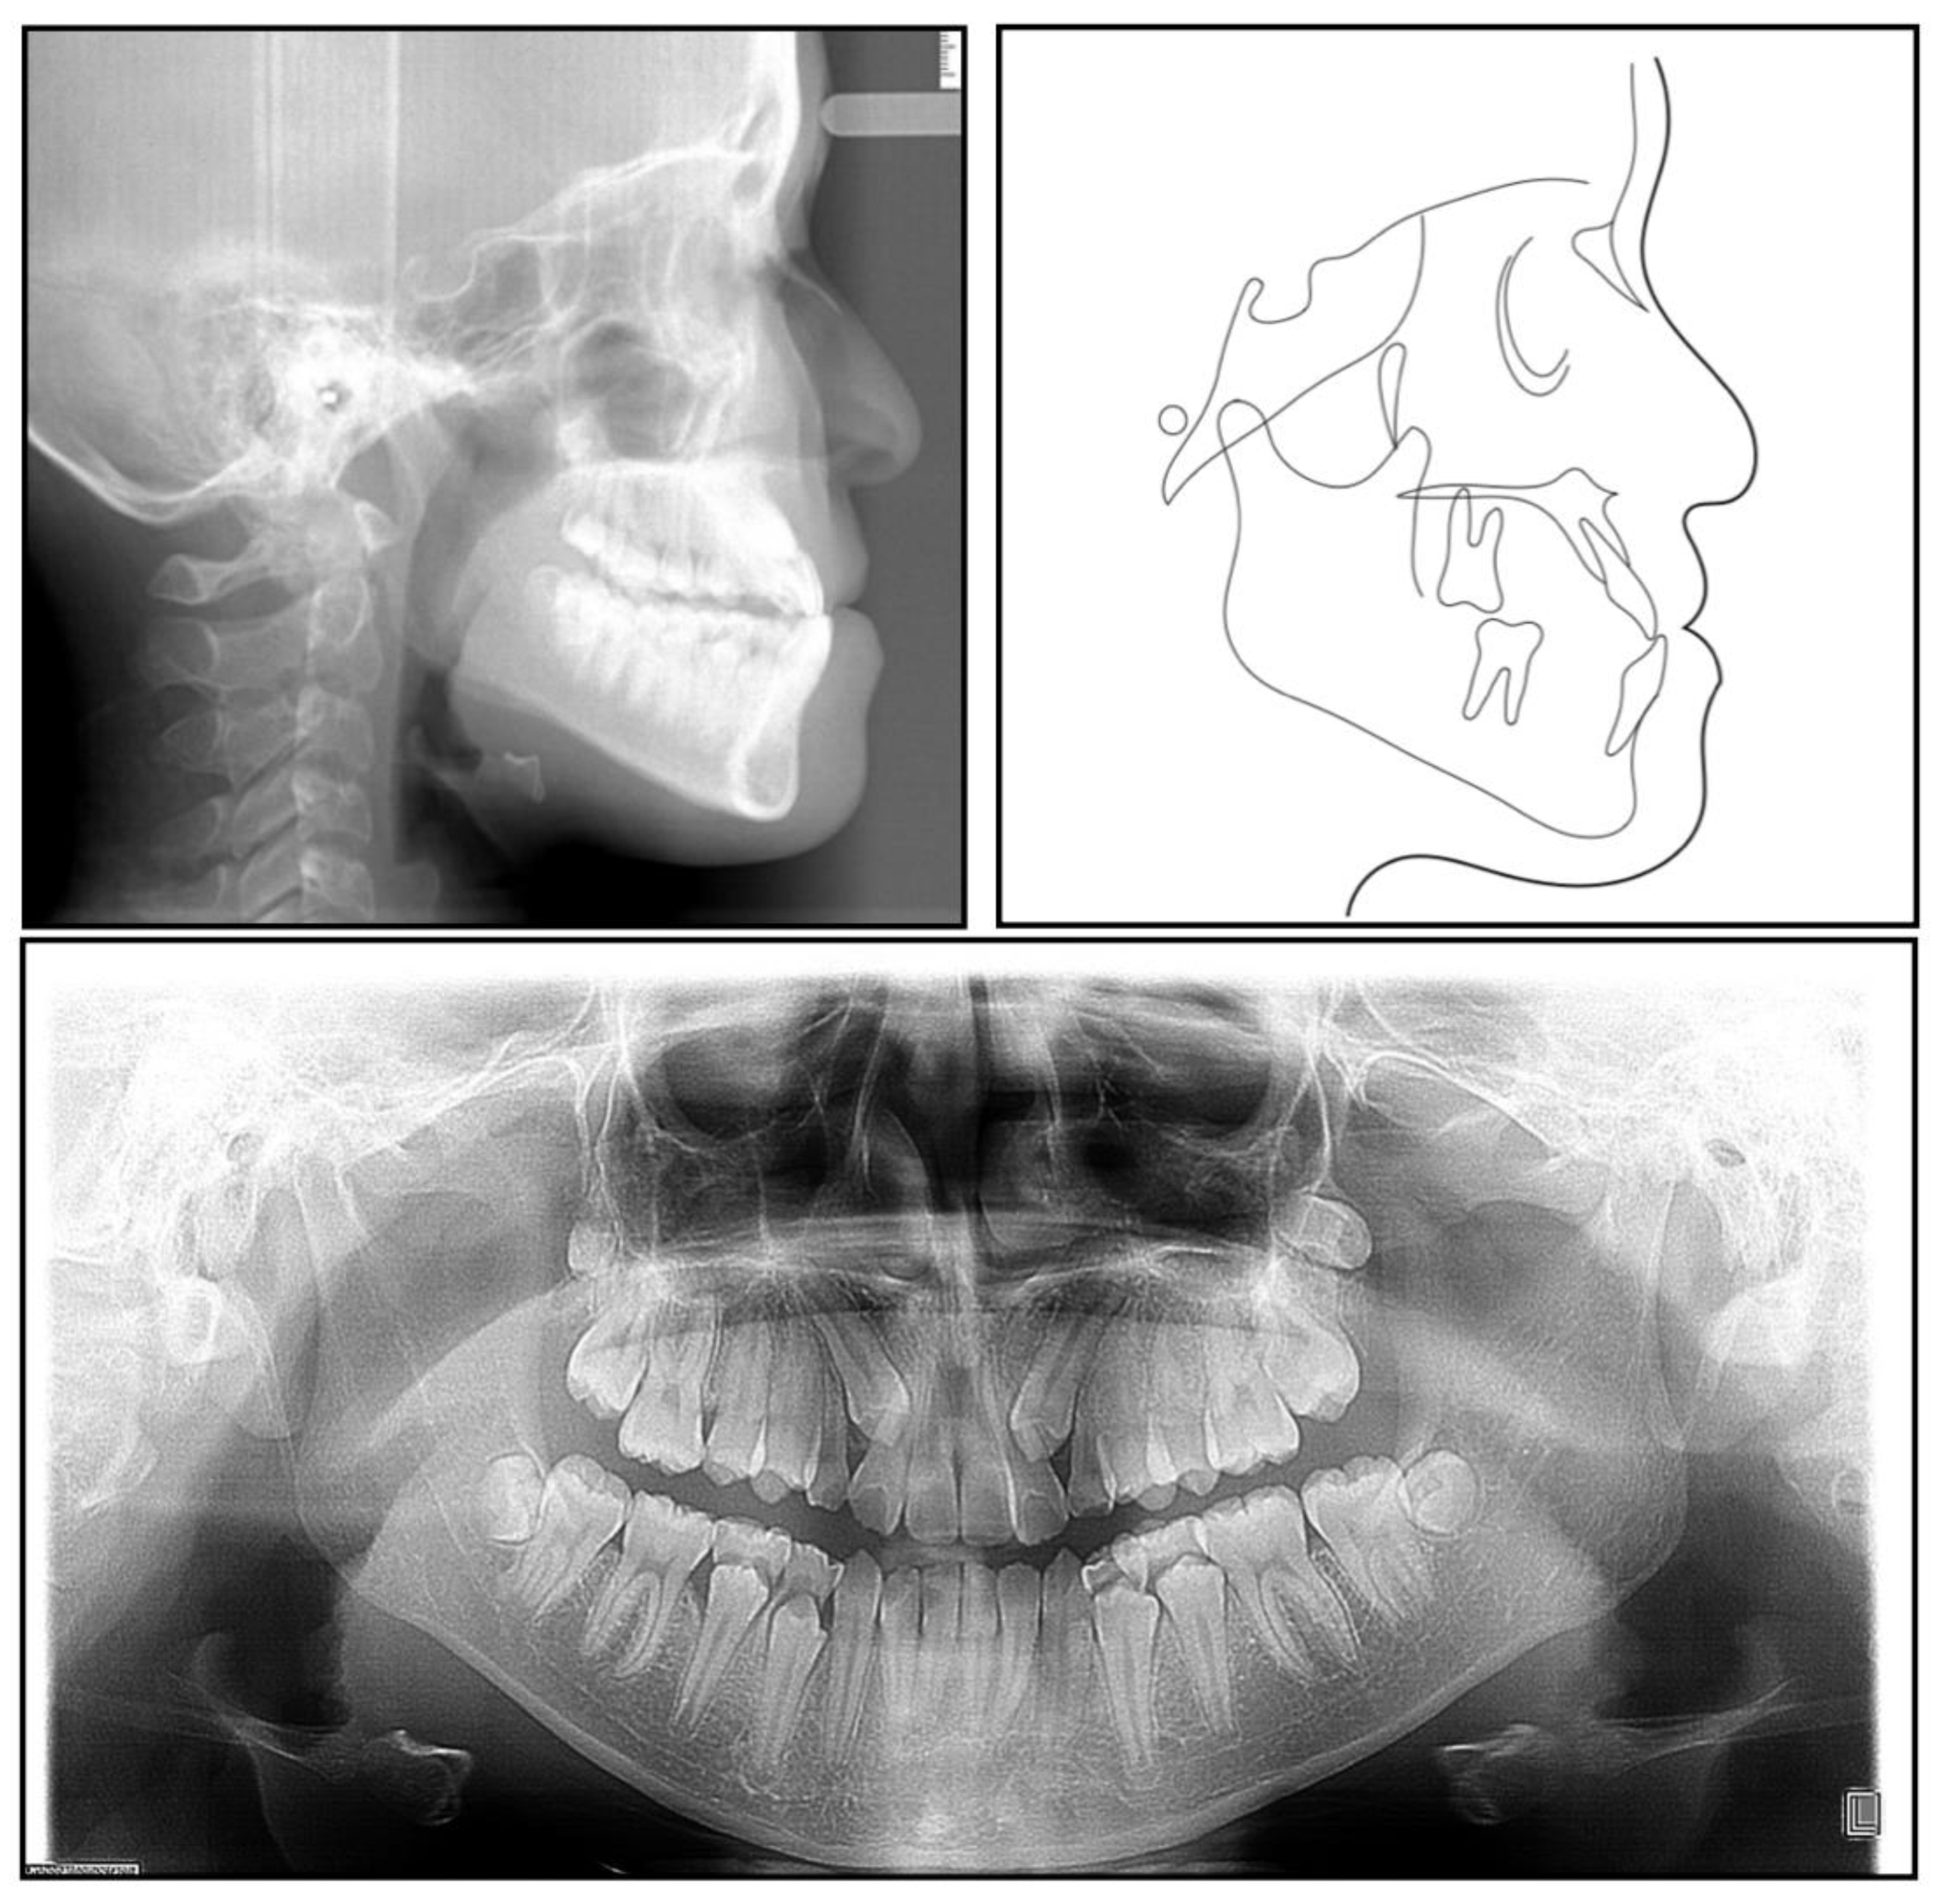

Figure 3. A pretreatment lateral cephalometric radiograph and tracing and a panoramic radiograph.

The panoramic radiograph showed that both the maxillary canines and all the third molars were impacted, and no significant periodontal support loss was found. The cephalometric analysis (Figure 3 and Table 1) showed a severe skeletal Class III relationship (ANB, −4.0°) with an insufficient developed maxilla (SNA, 77.2°). The maxillary incisors were relatively well-positioned, while the mandibular incisors were lingually inclined (U1-SN,104°; L1-MP, 86.5°) [8].